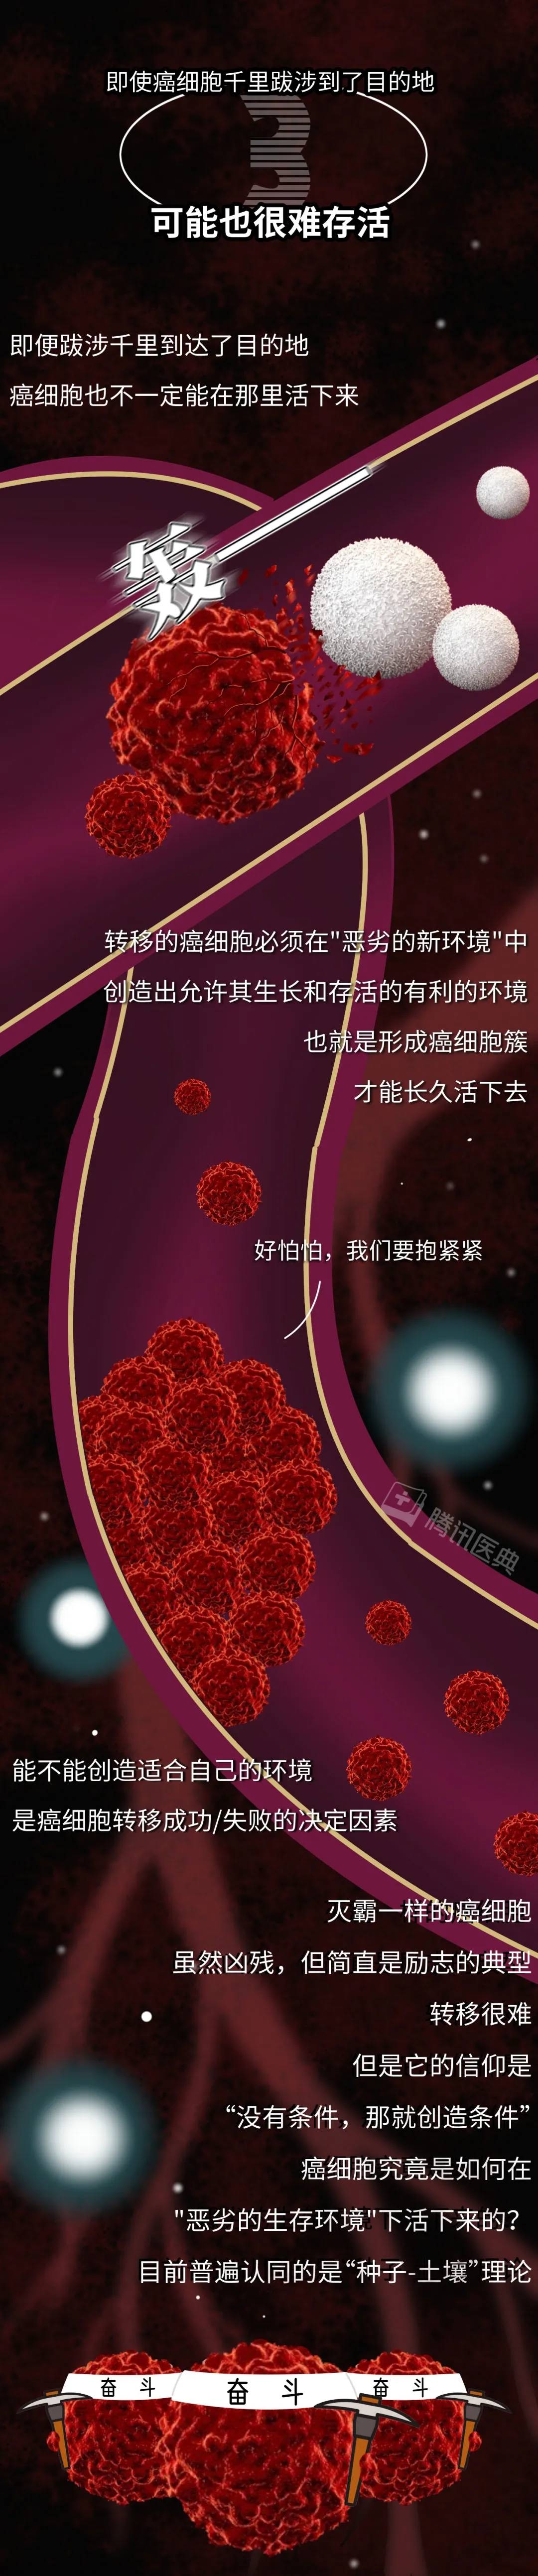

即便不幸确诊为癌症,肿瘤细胞已经发生了转移,也不要灰心,许多癌症病人接受规范化治疗后,可以像正常人一样活得好、活得久。